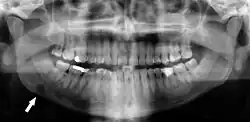

Panoramic radiographs have the capability to demonstrate a portion of the neck and display atheromas (calcifications in the carotid artery) which are an indication of both local and generalized (systemic) atherosclerosis. Atherosclerosis of the coronary arteries leading to myocardial infarction (heart attack), and atherosclerosis of the carotid artery leading to stroke are the number one and number three most common causes of death in the United States.[6]

There is interest to look at panoramic radiographs as a screening tool, however further data is needed with regards if it is able to make a meaningful difference in outcomes.[7]

Epidemiology: general public and high risk groups

Additional research projects have further determined the prevalence rate of these atheromas in the general population (3–5%)[8][9] and among high-risk groups (over 25% in: recent stroke victims,[10] individuals with obstructive sleep apnea syndrome,[11][12][13] postmenopausal women,[14] type 2 diabetics,[15][13][16] individuals with dilated cardiomyopathy,[17][13] and among individuals who have received radiotherapy directed at the neck,[18][19]). These findings have been corroborated by other several other researchers.[20][21][22][23][13]

Dental infection and atherosclerosis

Atherosclerosis is attributed to risk factors that include cigarette smoking, hyperlipidemia, obesity, diabetes mellitus, and hypertension (high blood pressure). These factors, however, do not fully account for the risk of disease. Atherosclerosis has been conceptualized as a chronic inflammatory response to endothelial cell injury[24] and dysfunction possibly arising from chronic dental infection. In 2010, using the previously validated Mattila panoramic radiographic index to quantify the totality of dental infection (i.e., periapical and furcal lesions, pericoronitis sites, carious tooth roots, teeth with pulpal caries, and vertical bony defects), Friedlander's group determined that individuals with carotid artery atheromas on their panoramic radiographs had significantly greater amounts of dental infection/inflammation than atherogenic risk-matched controls devoid of radiographic atheromas.[25][26] While the Mattila index had been previously used to relate the extent of dental infection to coronary artery disease, this research is the first to link the full range of dental disease that it measures to panoramic radiographs evidencing calcified carotid artery atherosclerosis.